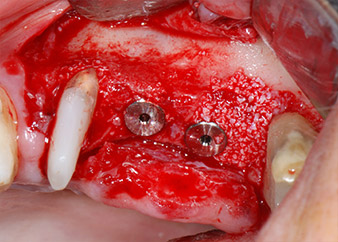

ready for the cover screws

Fig. 12: Both implants in place and ready for the cover screws.